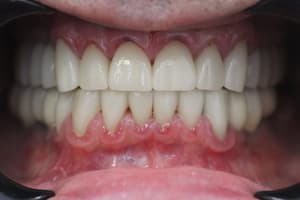

Нерівномірна патологічна стирання зубів, гіперфункції м'язів, відсутність зубів. Відновлення естетики та функціональності зубощелепного ряду верхньої та нижньої щелеп.

Виражений бруксизм, стирання зубів після гнатологічного обстеження лікар вирішив завищувати прикус до 2 мм і фіксацію центрального співвідношення. Встановлено коронки E.max на свої зуби. Коронки на імплантах виготовлені з металокераміки для запобігання сколам.

Всі роботи не пройшли жодної обробки і не застосовувався жоден фільтр, з великої кількості портфоліо лікарів, ми виставляємо лише малу частину прикладів робіт»